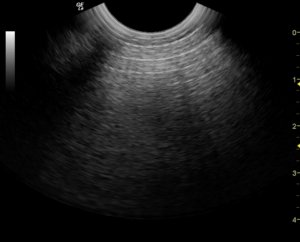

Neumoperitoneo en ecografia. En principio se aprecian múltiples líneas paralelas y equidistantes entre si. Estas lineas de interpretan como la presencia de aire.